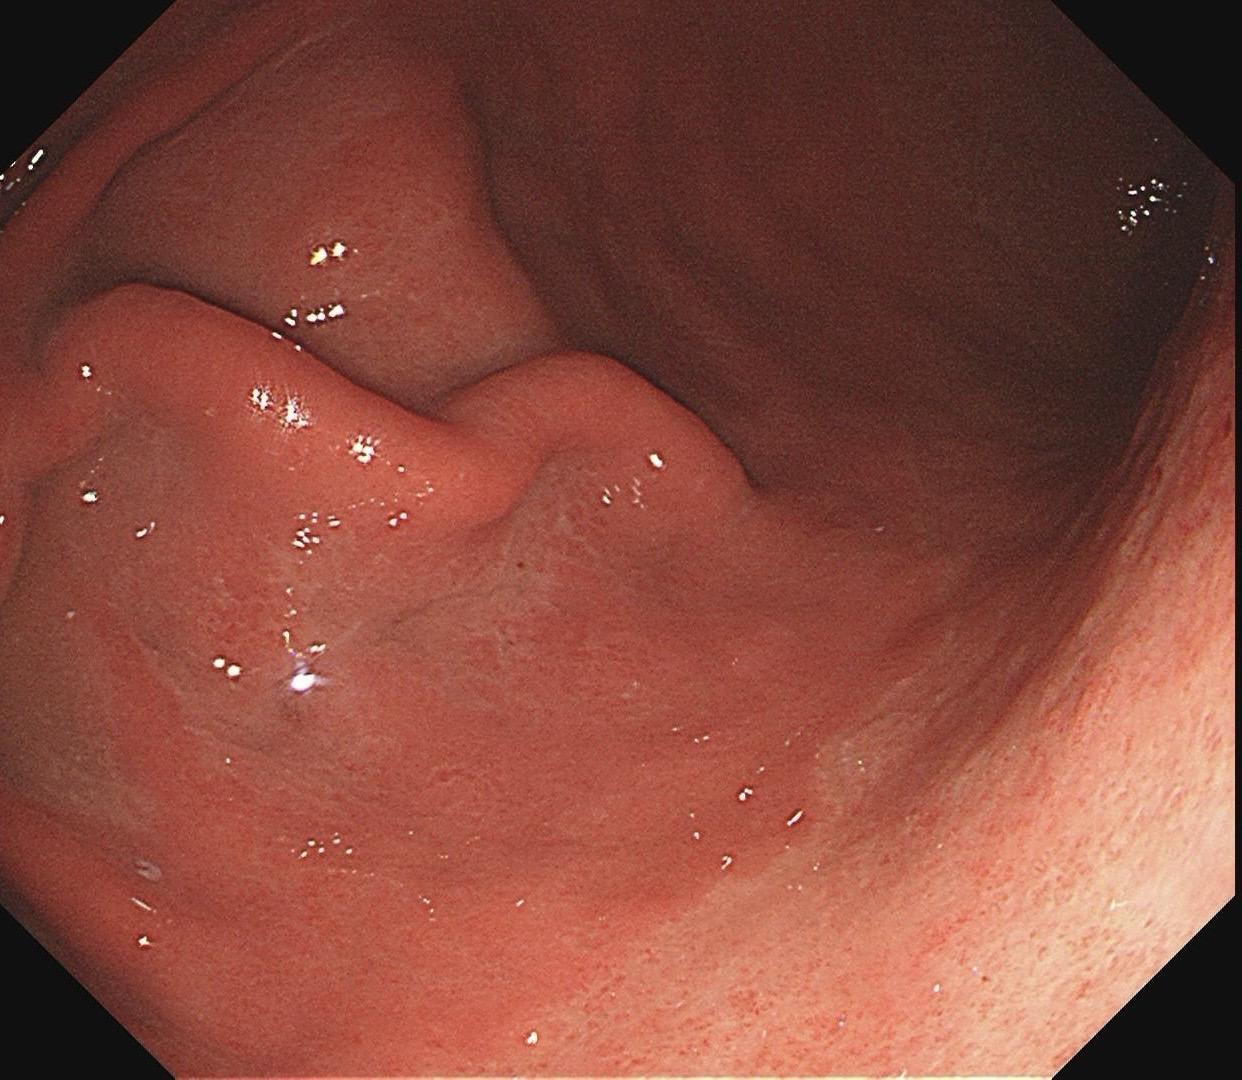

男,61岁,胃巨大褪色调病变。答案在最后一张图片,你猜对了吗? 患者因上腹部饱胀行胃镜检查,Hp阴性背景,胃窦至贲门下见一巨大褪色调病变,边界清晰,病变相对表浅,未见明显溃疡及隆起,胃壁较柔软,充气顺应性佳,予多点活检确诊,拟外科手术行全胃切除。做这么多年胃镜,还是第一次遇到这样的……